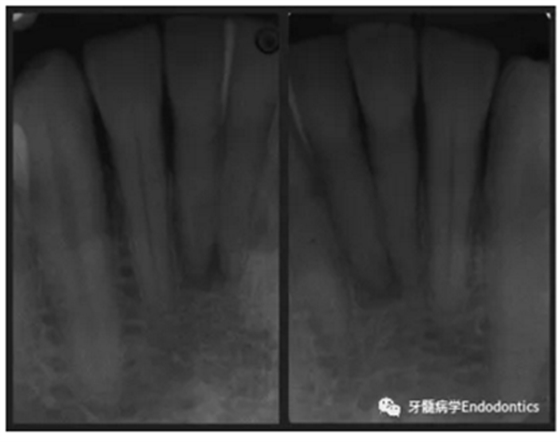

31、41叩痛明顯,牙冠變色(圖1)。溫度和牙髓電活力測(cè)試無(wú)反應(yīng)。兩張從不同角度拍攝的x線(xiàn)片顯示,相對(duì)于側(cè)切牙,雙側(cè)下中切牙都有嚴(yán)重的根管鈣化(圖2)。41有明顯根尖周暗影,31根尖周暗影不明顯。為進(jìn)一步證實(shí)31是否存在根尖周病變,同時(shí)精細(xì)觀(guān)察31、41的復(fù)雜結(jié)構(gòu),根據(jù)歐洲牙髓病學(xué)會(huì)CBCT應(yīng)用指南(2014),對(duì)患牙拍攝小視野、高分辨率CBCT。CBCT影像證實(shí)31、41均伴有根尖周炎和嚴(yán)重的根管鈣化(圖3)。距離根尖4mm可見(jiàn)根管影像。 由于患牙根管解剖結(jié)構(gòu)較為復(fù)雜,筆者決定使用特殊設(shè)計(jì)的微型鉆頭(直徑0.85mm)進(jìn)行“數(shù)字化導(dǎo)航牙髓治療”。 因此對(duì)下頜進(jìn)行口內(nèi)掃描(圖4)。用coDiagnostixTM軟件(Dental Wings Inc.,Montreal,Canada)將CBCT和口內(nèi)掃描的數(shù)據(jù)進(jìn)行處理,該軟件主要用于引導(dǎo)種植。通過(guò)該軟件對(duì)兩個(gè)掃描圖像進(jìn)行疊加后,虛擬鉆頭尖端沿牙長(zhǎng)軸對(duì)準(zhǔn)根管下段可見(jiàn)部分(圖5)。三維檢查虛擬鉆的正確位置。

圖2. 31、41X線(xiàn)影像。

圖3.下頜前牙CBCT影像。